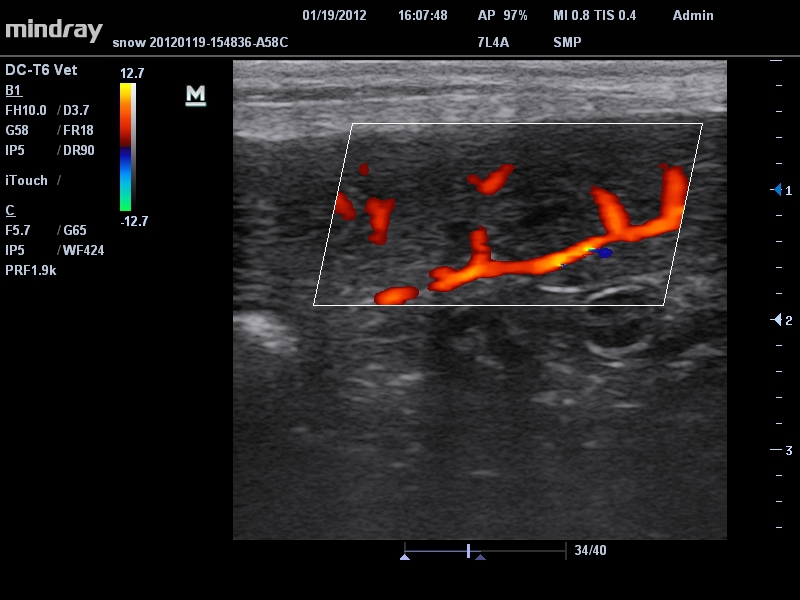

Mindray DC-T6

Ультразвуковая система Mindray DC-T6 – это инновационный аппарат для проведения высокого уровня диагностики с качественной визуализацией и широким спектром применения. Платформа рекомендована для использования в коммерчески многопрофильных медицинских учреждениях и государственных лечебных клиниках.

Энергетический допплер:

Да

• Режимы сканирования: B/M/CFM/PDI/Направленный PDI/PW, HPRF, Тканевая гармоника, М- и цветной М-режим.

• Линейный ультразвуковой датчик Mindray 7L4A